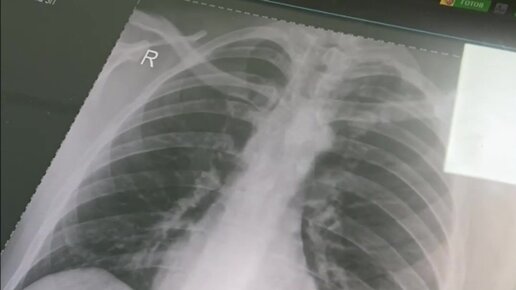

Как часто можно выполнять рентген?